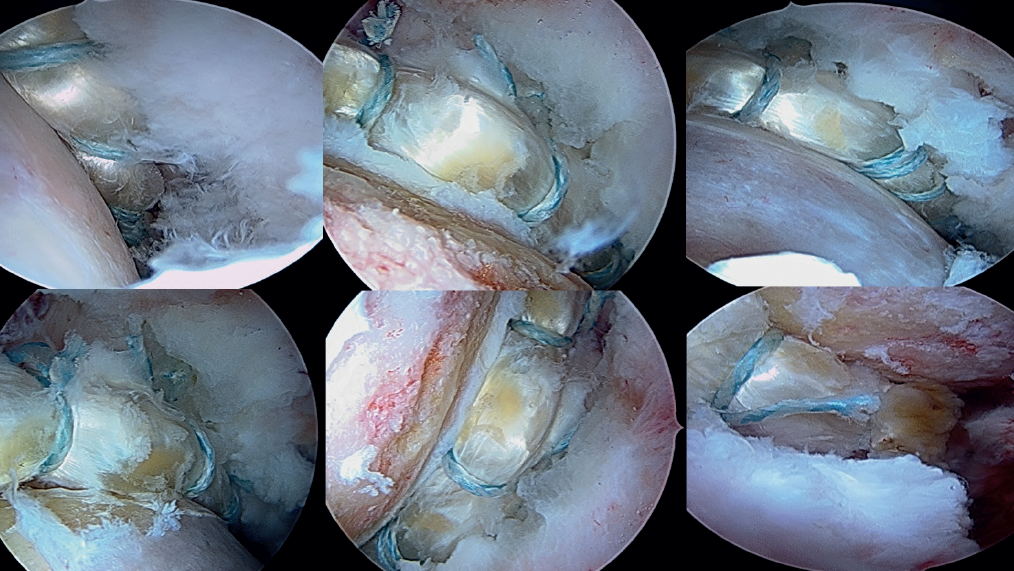

Insertion of the graft

Forceps are inserted from the posterior portal, taking care that they lie posterior to the last anchoring, and from the anterior modified portal we introduce the suture anchored to the anterior portion of the graft, likewise taking care that it lies anterior to the most anterior anchoring. Once within the joint, this suture is grasped with the forceps inserted from the posterior portal, and then traction is exerted posterior until it emerges from the posterolateral portal. Lastly, traction is continued to introduce the graft, making it emerge through the posterolateral portal. At this point, the anchoring preassembled in the graft is guided towards the pre-drilling made and is inserted, thereby fixing the most anterior portion of the graft in the case of using a knotless anchoring or extracting the suture and threading the tendon to then perform a knotted technique(Figure 12). After positioning and fixation of the most anterior portion of the graft, the filaments are passed around the graft in sequence, and are tightened little by little, maintaining traction from the posterolateral portal, and fixing and positioning the entire plasty from anterior to posterior (Figures 13 and 14). Once all these steps have been completed, the excess graft is radiofrequency amputated from the posterolateral portal. Lastly, the hip is evaluated dynamically in all the planes of motion, checking fixation, the position of the graft, and recreation of the sealing effect at the femoral head-neck junction with the acetabular labrum (Figure 15).